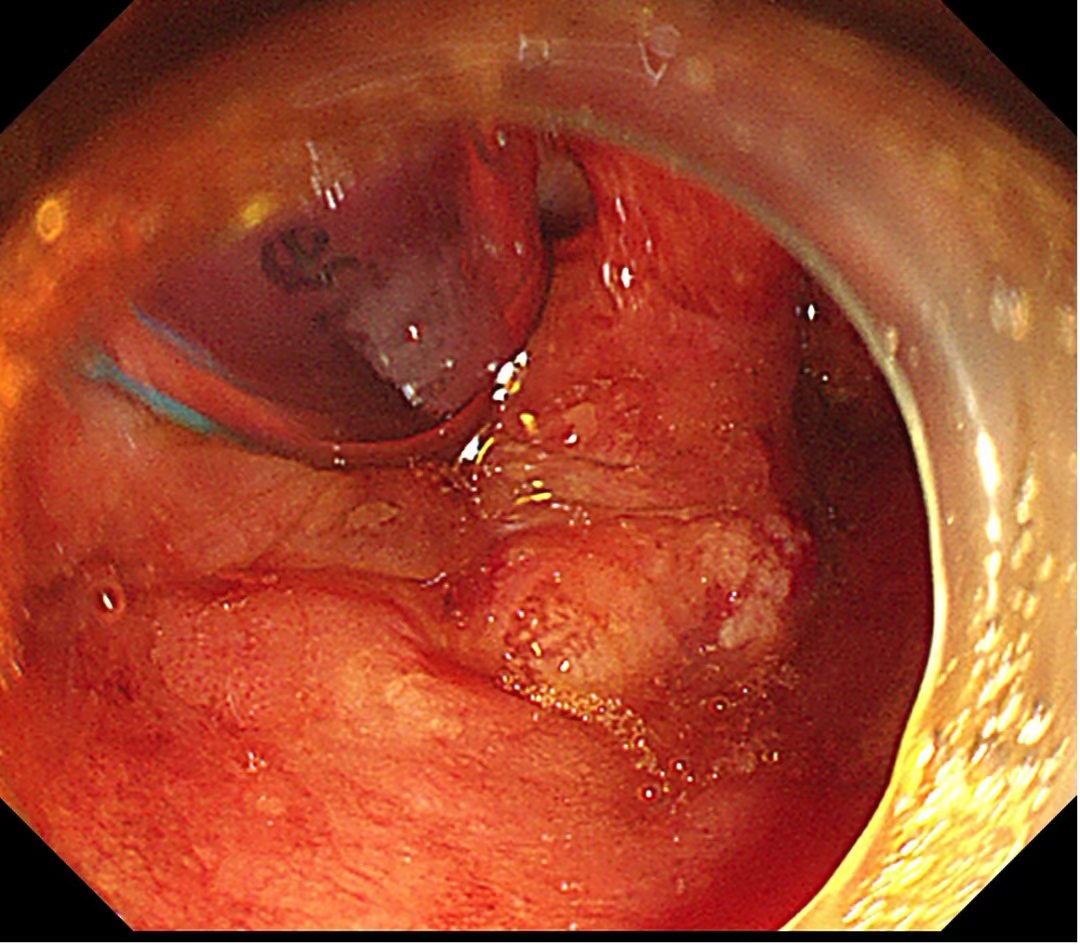

食管病灶

1.(食管33处)食管糜烂型鳞状细胞癌,Ⅱ级,肿瘤大小0.6×0.3cm,癌组织局限于黏膜内(M2);淋巴管及血管内未见癌栓;送检组织四周及基底部切缘未见癌组织。免疫组化结果显示:CD34(未见癌栓),D2-40(未见癌栓),Desmin(平滑肌+),E-cadherin(+),Ki-67(index≈40%),P53(+,突变型)。